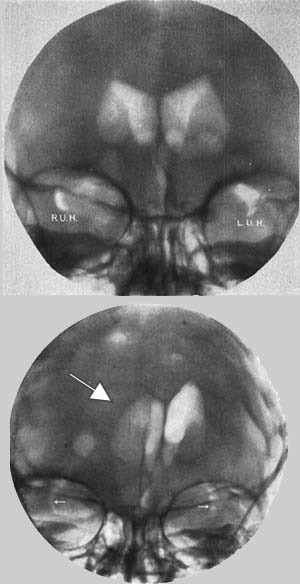

図1. (気)脳室造影.(上図)空気が充盈した側脳室が左右対称の透亮像として認められる[4].(下図)右側頭葉腫瘍.側脳室が左に強く圧排され(→),右大脳半球に占拠性病変があることを示している[5].

1918年,Dandyが発表した(気)脳室造影法(pneumoventriculography, ventriculo-graphy) は[→原著論文],脳室を直接穿刺して40~300mL空気を注入する方法で,大泉門がまだ開いている小児ではここを穿刺できるが,成人では頭蓋穿頭が必要であった.翌1919年には,腰椎穿刺によって空気を注入し,頭蓋内くも膜下腔,脳槽を造影する気脳造影法(encephalography,pneumoencephalography)を発表した[→原著論文](図1).いずれも侵襲の大きな検査であるが,その後CTが登場するまでの約半世紀にわたって脳血管造影とともに,神経放射線診断学の重要な武器となった.